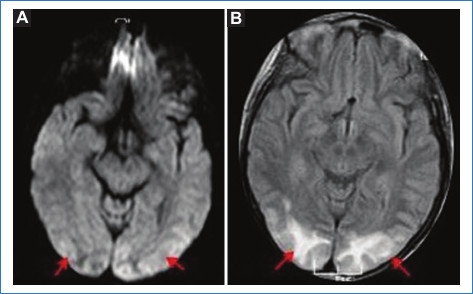

RM: puede haber áreas con edema vasogénico representadas por hiperintensidad en T2 e hipointensidad en T1. Puede haber áreas de HSA. La angio-RM o la angio-TC demuestran estrechamientos vasculares multifocales en forma difusa que se suelen resolver a los tres meses (Fig. 3)4.

Angiografía: se observan estenosis multifocales reversibles de los vasos de segundo y tercer orden de la circulación anterior y posterior. Puede persistir durante días y semanas, y en caso de progresar puede asociarse a estenosis de vasos más proximales (va de distal a proximal). Los estudios realizados en una fase temprana no suelen documentar alteraciones, dado que la máxima vasoconstricción de las ramas de la arteria cerebral media se documenta alrededor de los 16 días después del inicio clínico4,17.